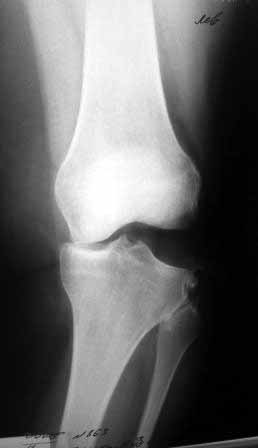

Сегодня на приеме была больная 27 лет, вес 120кг. Травма 7 лет назад - ДТП. Была ЧМТ, двухсторонний перелом пилона, обширные рваные раны бедер, голеней. Судя по нынешней картине - вывих левой голени.

Ходит практически не хромая, жалобы на неустойчивость голени при ходьбе. При стресс тестах - грубейшая несостоятельность связочного аппаратаколенного сустава. Хотелось бы услышать мнение о целесообразности пластического восстановления связок после столь длительного периоданестабильности сустава.С уважением,Leonid m

Сделайте МРТ. При таком р-гене возможен разрыв задне-латерального комплекса с выраженной нестабильностью. Тактика - пластика ЗКС, ЛКС.